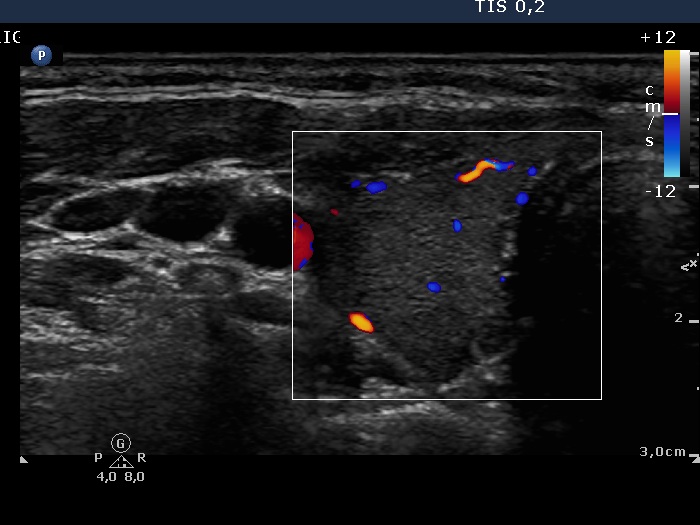

Third examination 24 months after initial investigation (3rd row of images)

Clinical data: The thyrostatic therapy was stopped 13 months ago. The patient had no complaints.

Palpation: unchanged.

Results of blood tests: euthyroidism (TSH 0.52 mIU/L, FT4 14.6 pM/L).

Ultrasonography: The size of the thyroid decreased further. The echo structure and the vascularization became normal.

Suggestion: to check the thyroid function every year, in the event of complaints or pregnancy at once.

Comment. This case demonstrates typical course of non-relapsing Graves disease. The change in hormone levels and in the ultrasound pattern are parallel.